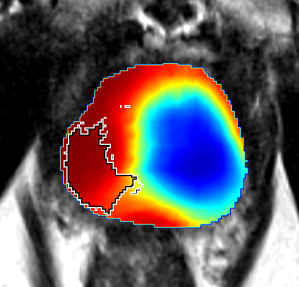

Qualitative Evaluation: Figure 4 shows the same slice as in Figure 2 with aligned T2W, ADC, and histopathology images, and prediction results using current state-of-the-art method [4], our CorrSigNet() and CorrSigNet(T2W, ADC, ) models. It may be noted that [4] fails to detect the cancerous regions on the left and right of the images, while the CorrNet representations alone can identify the cancer regions, and when combined with T2W and ADC images, they predict the cancer regions with high probability. It may also be noted that CorrSigNet(T2W, ADC, ) shows fewer false positives than [4]. This example shows the strength of learning correlated MRI signatures in identifying subtle, and sometimes MRI-invisible cancers. Figure 5 shows more example slices from different patients, comparing the state-of-the-art approach [4] and our prediction results with CorrSigNet(T2W, ADC, ). We note that our model with correlated features (1) can identify subtle and smaller cancer regions, (2) have better overlap with ground truth cancer labels, and (3) have fewer false positives.